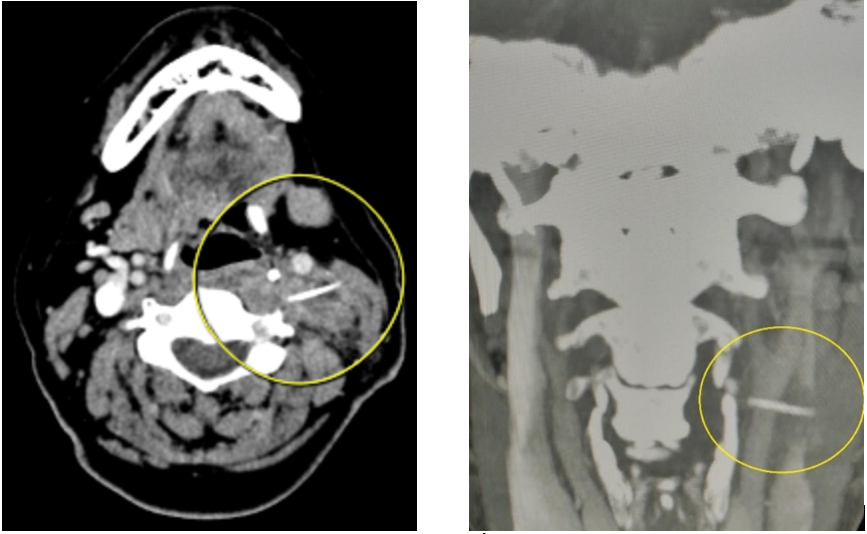

(Baothanhhoa.vn) – Bệnh viện Đa khoa tỉnh Thanh Hóa vừa tiếp nhận và phẫu thuật cấp